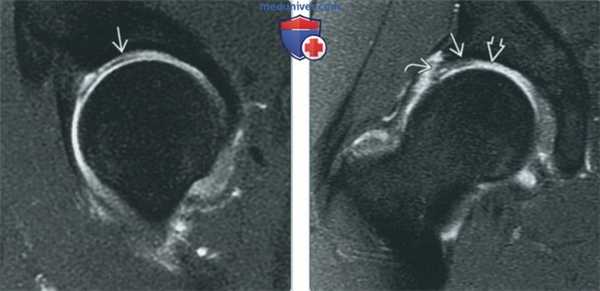

(Слева) МР-артрография в режиме Т1ВИ FS, косоаксиальный срез, пациент с жалобами на рецидив боли после артроскопической коррекции разрыва суставной губы и резекции костного выступа: определяется, что восстановленный участок суставной губы имеет выражено неравномерный контур, однако является интактным, о чем свидетельствует отсутствие затека контраста в суставную губу. Для выявления рецидивирующего разрыва суставной губы лучше выполнить МР-артрографию в режиме Т1ВИ.

(Справа) МР-артрография в режиме Т1ВИ FS, косоаксиальный срез, этот же пациент: выявляется отслоение суставной губы ниже восстановленного участка. Область, подвергшаяся остеохондропластике, ничем не примечательна. (Слева) МР-артрография в режиме Т2ВИ FS, коронарный срез, этот же пациент: суставная капсула растянута, восстановленный участок суставной губы имеет неровный контур и содержит зону, интенсивность сигнала которой соответствует интенсивности сигнала от жидкости. Для дифференциации грануляционной ткани и контрастного препарата в разрыве суставной губы, необходим режим Т1.

(Справа) МР-артрография в режиме PD FS, сагиттальный срез, этот же пациент: отмечается неровный контур восстановленного участка суставной губы, а также локальное истончение суставного хряща. Область, подвергшаяся остеохондропластике, ничем не примечательна.